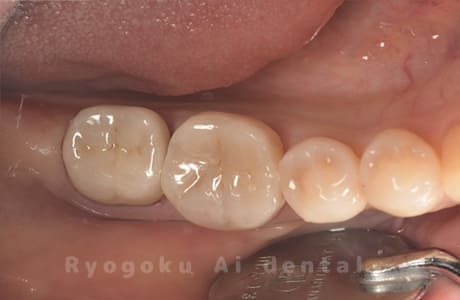

Case11

-

- 原因

- インレー2次カリエス、ならびにインレー脱離

- 治療内容

- セラミッククラウン、セラミックインレー

- 治療費用

- 123,000円×2(セラミッククラン)、77,000円(セラミックインレー)

銀歯が取れて、ご来院された患者様です。奥歯2本をセラミッククラウン、手前の小臼歯をセラミックインレーで治療を行いました。

<リスク・副作用>

過度の咬合や衝撃で割れることがあります。